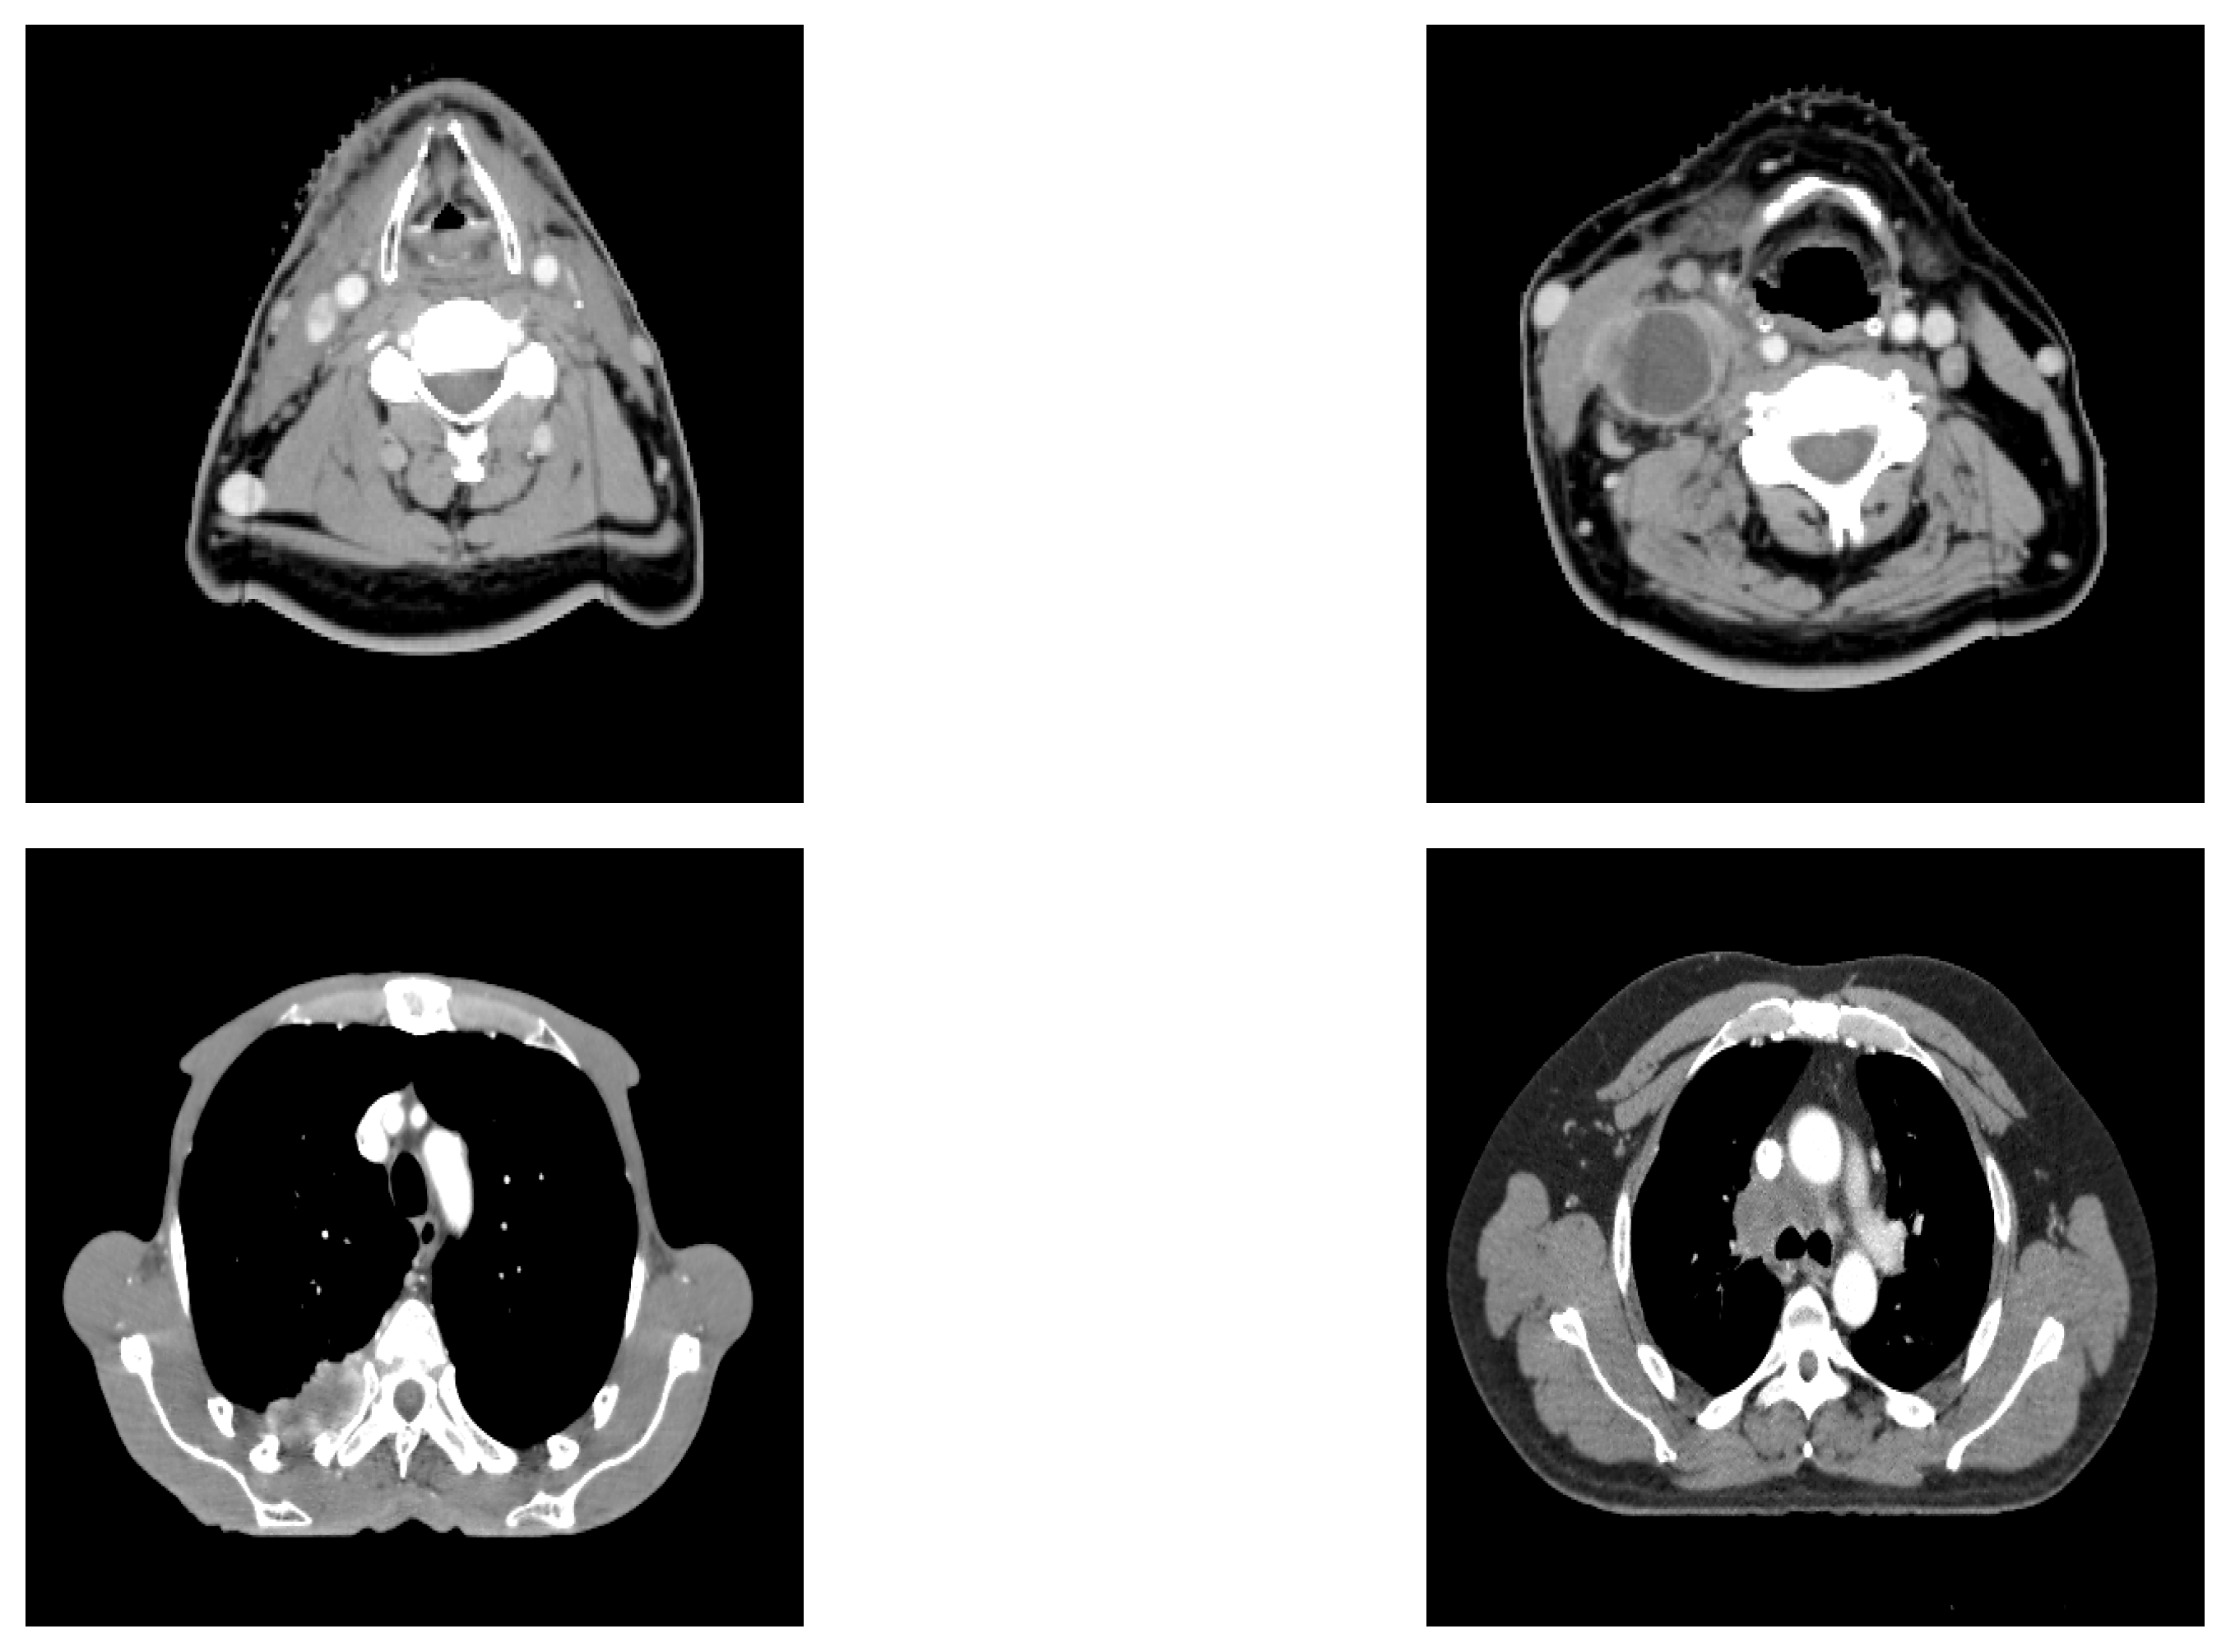

The results achieved during the tests are displayed in this section. Reconstructed images are mainly used in order to show the relevance of extracted features for the prediction. Therefore, their performance is not very important here, because the objective is the prediction of recurrence. The original images and reconstructed ones are featured in Figure 3. We can see that the reconstructed images are similar to the input images, meaning that our network is able to recover input images.

The loss of information generates uncertainty in each image. A possible improvement would be to use a fuzzy image processor to improve the quality of the obtained images, as described in [33].

Figure 3. Input images: original images (left) vs. reconstructed images (right).